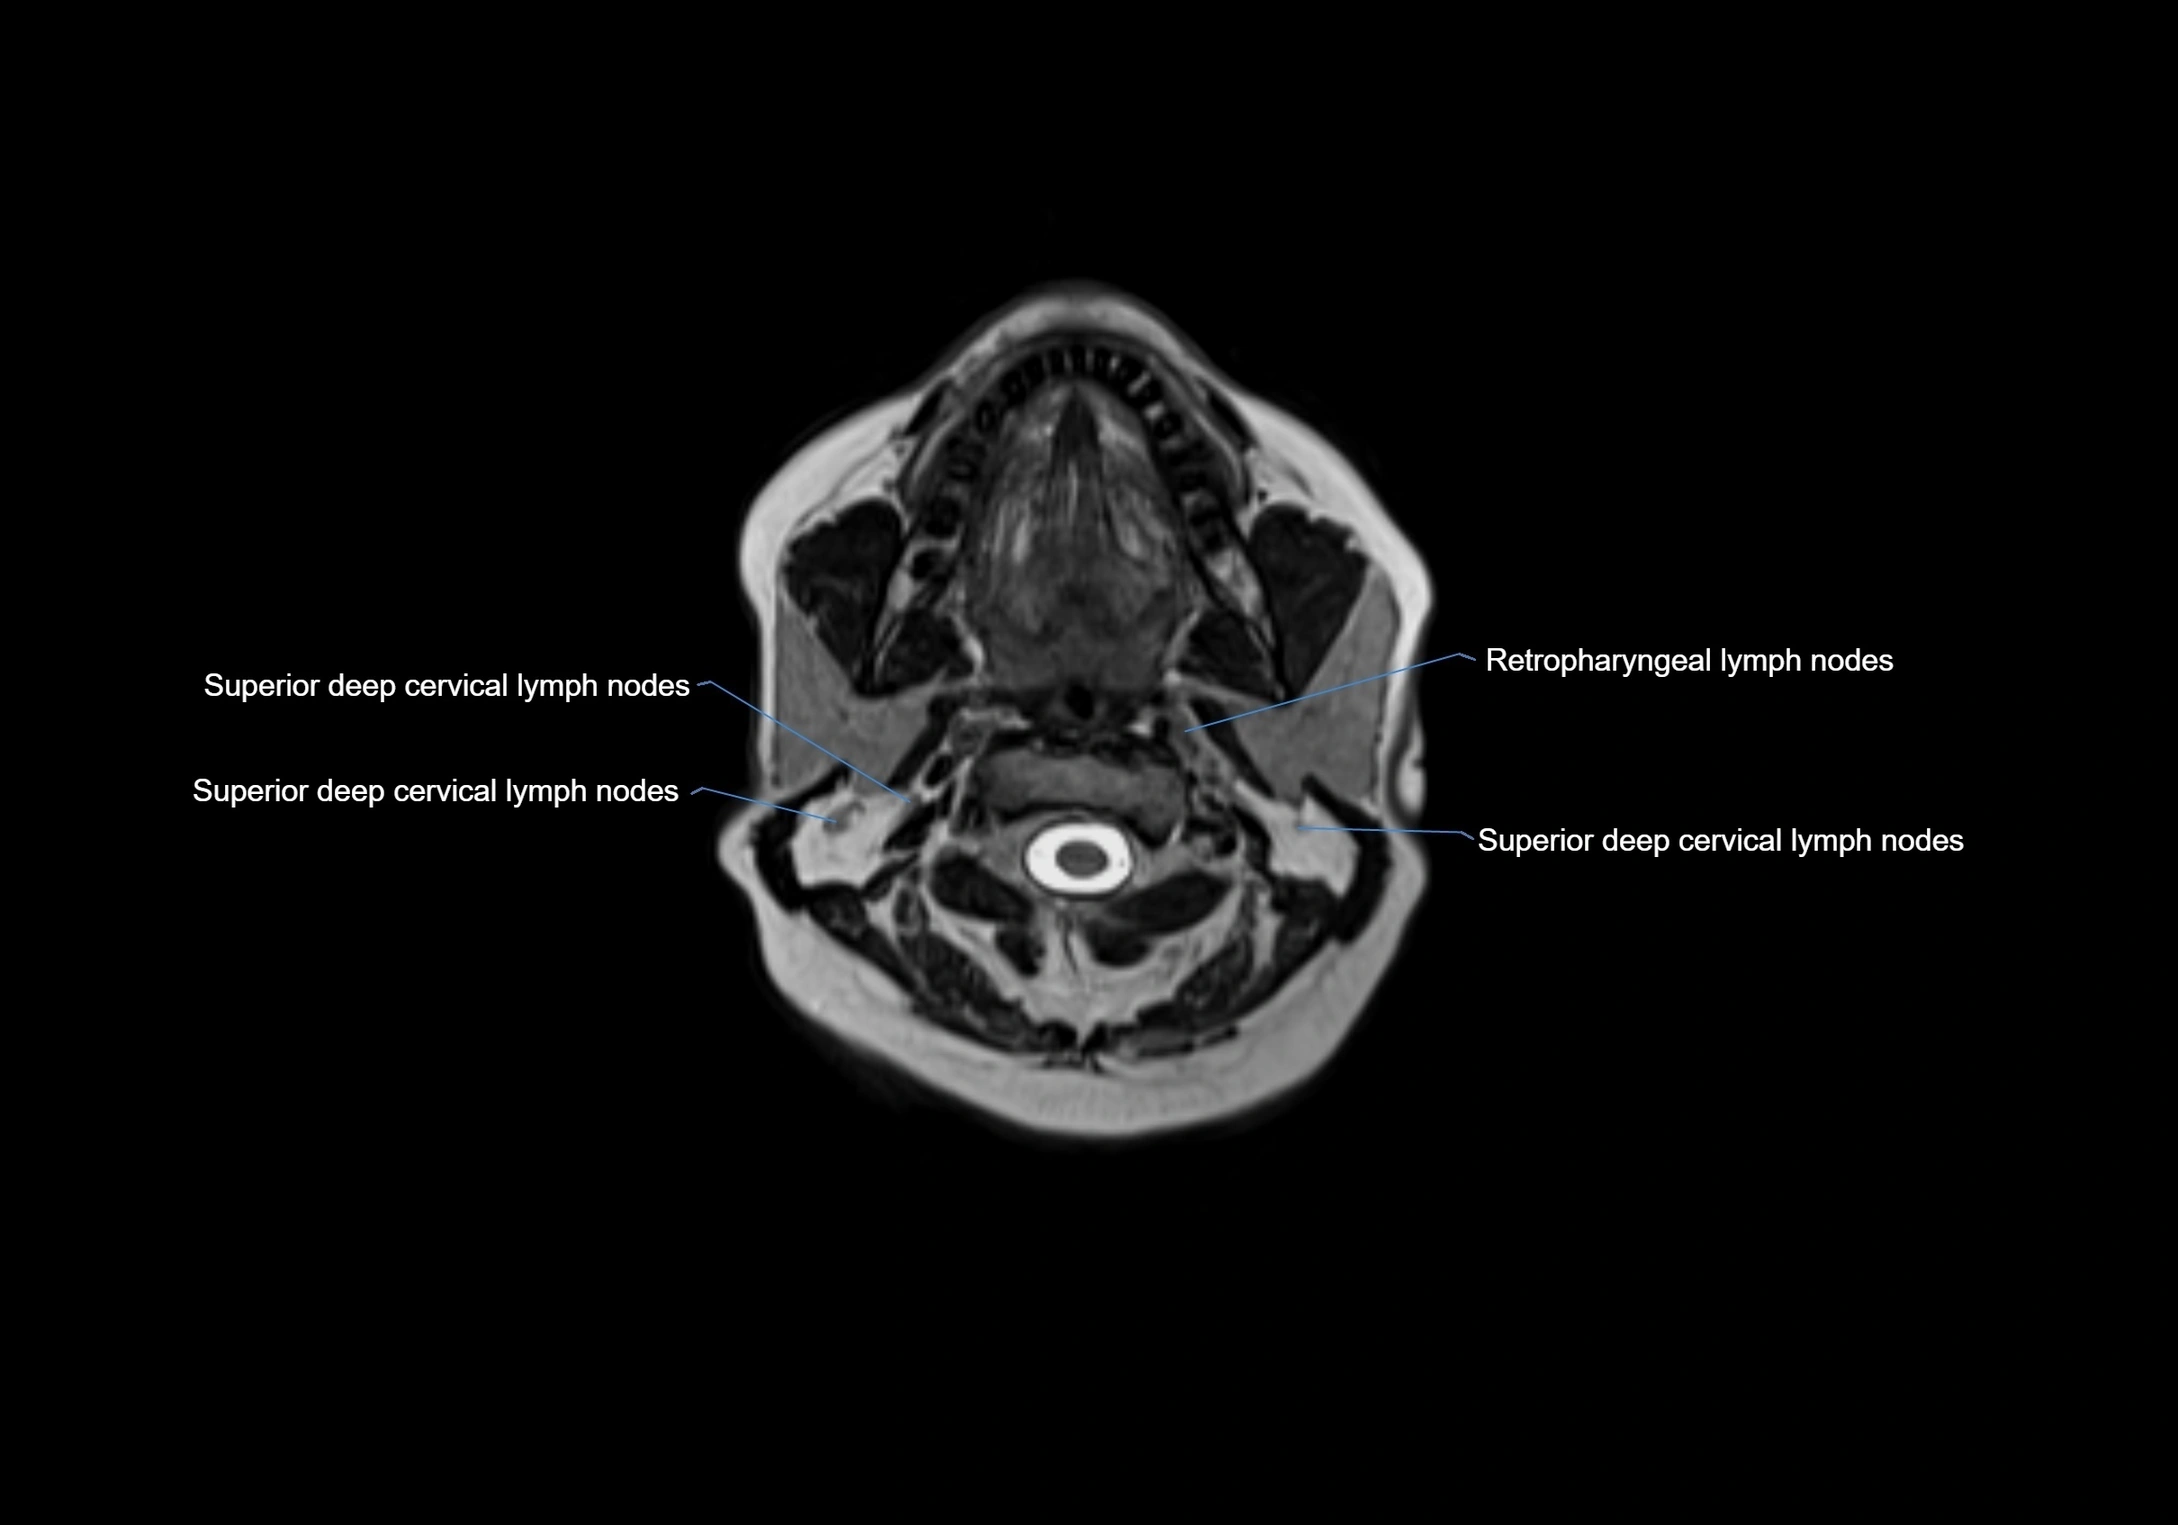

MRI Appearance

T1-weighted images:

• Normal accessory nodes appear as small, oval hypointense to intermediate signal structures within subcutaneous fat

• Surrounded by hyperintense fat, enhancing contrast for visualization

• Pathological nodes may appear enlarged or rounded, sometimes with cortical thickening

T2-weighted images:

• Nodes show intermediate signal, with surrounding fat bright

• Useful for detecting edema, inflammation, or infiltration

• Fatty hilum may appear slightly hyperintense relative to cortex

MRI images

image